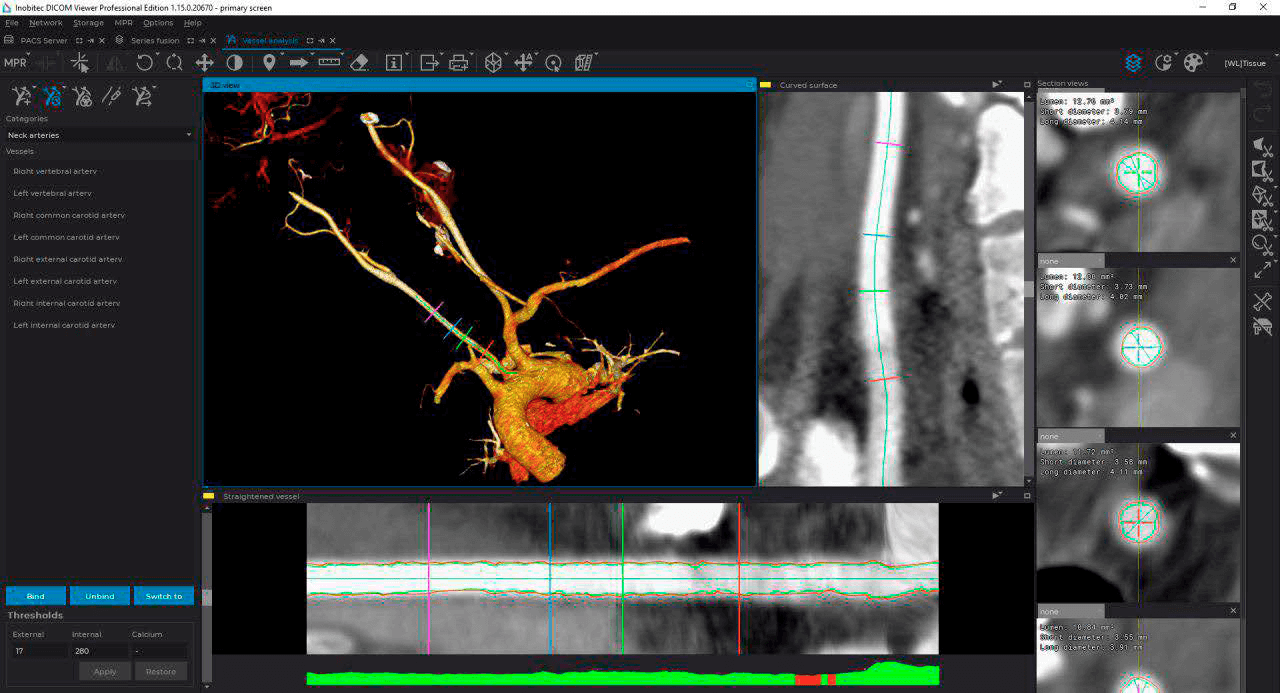

Advanced capabilities for working with 3D reconstructions

Advanced multiplanar reconstruction capabilities